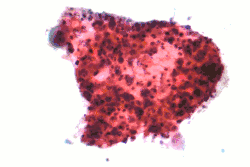

Micrograph of a squamous carcinoma, a type of non-small-cell lung carcinoma, FNA specimen, Pap stain.